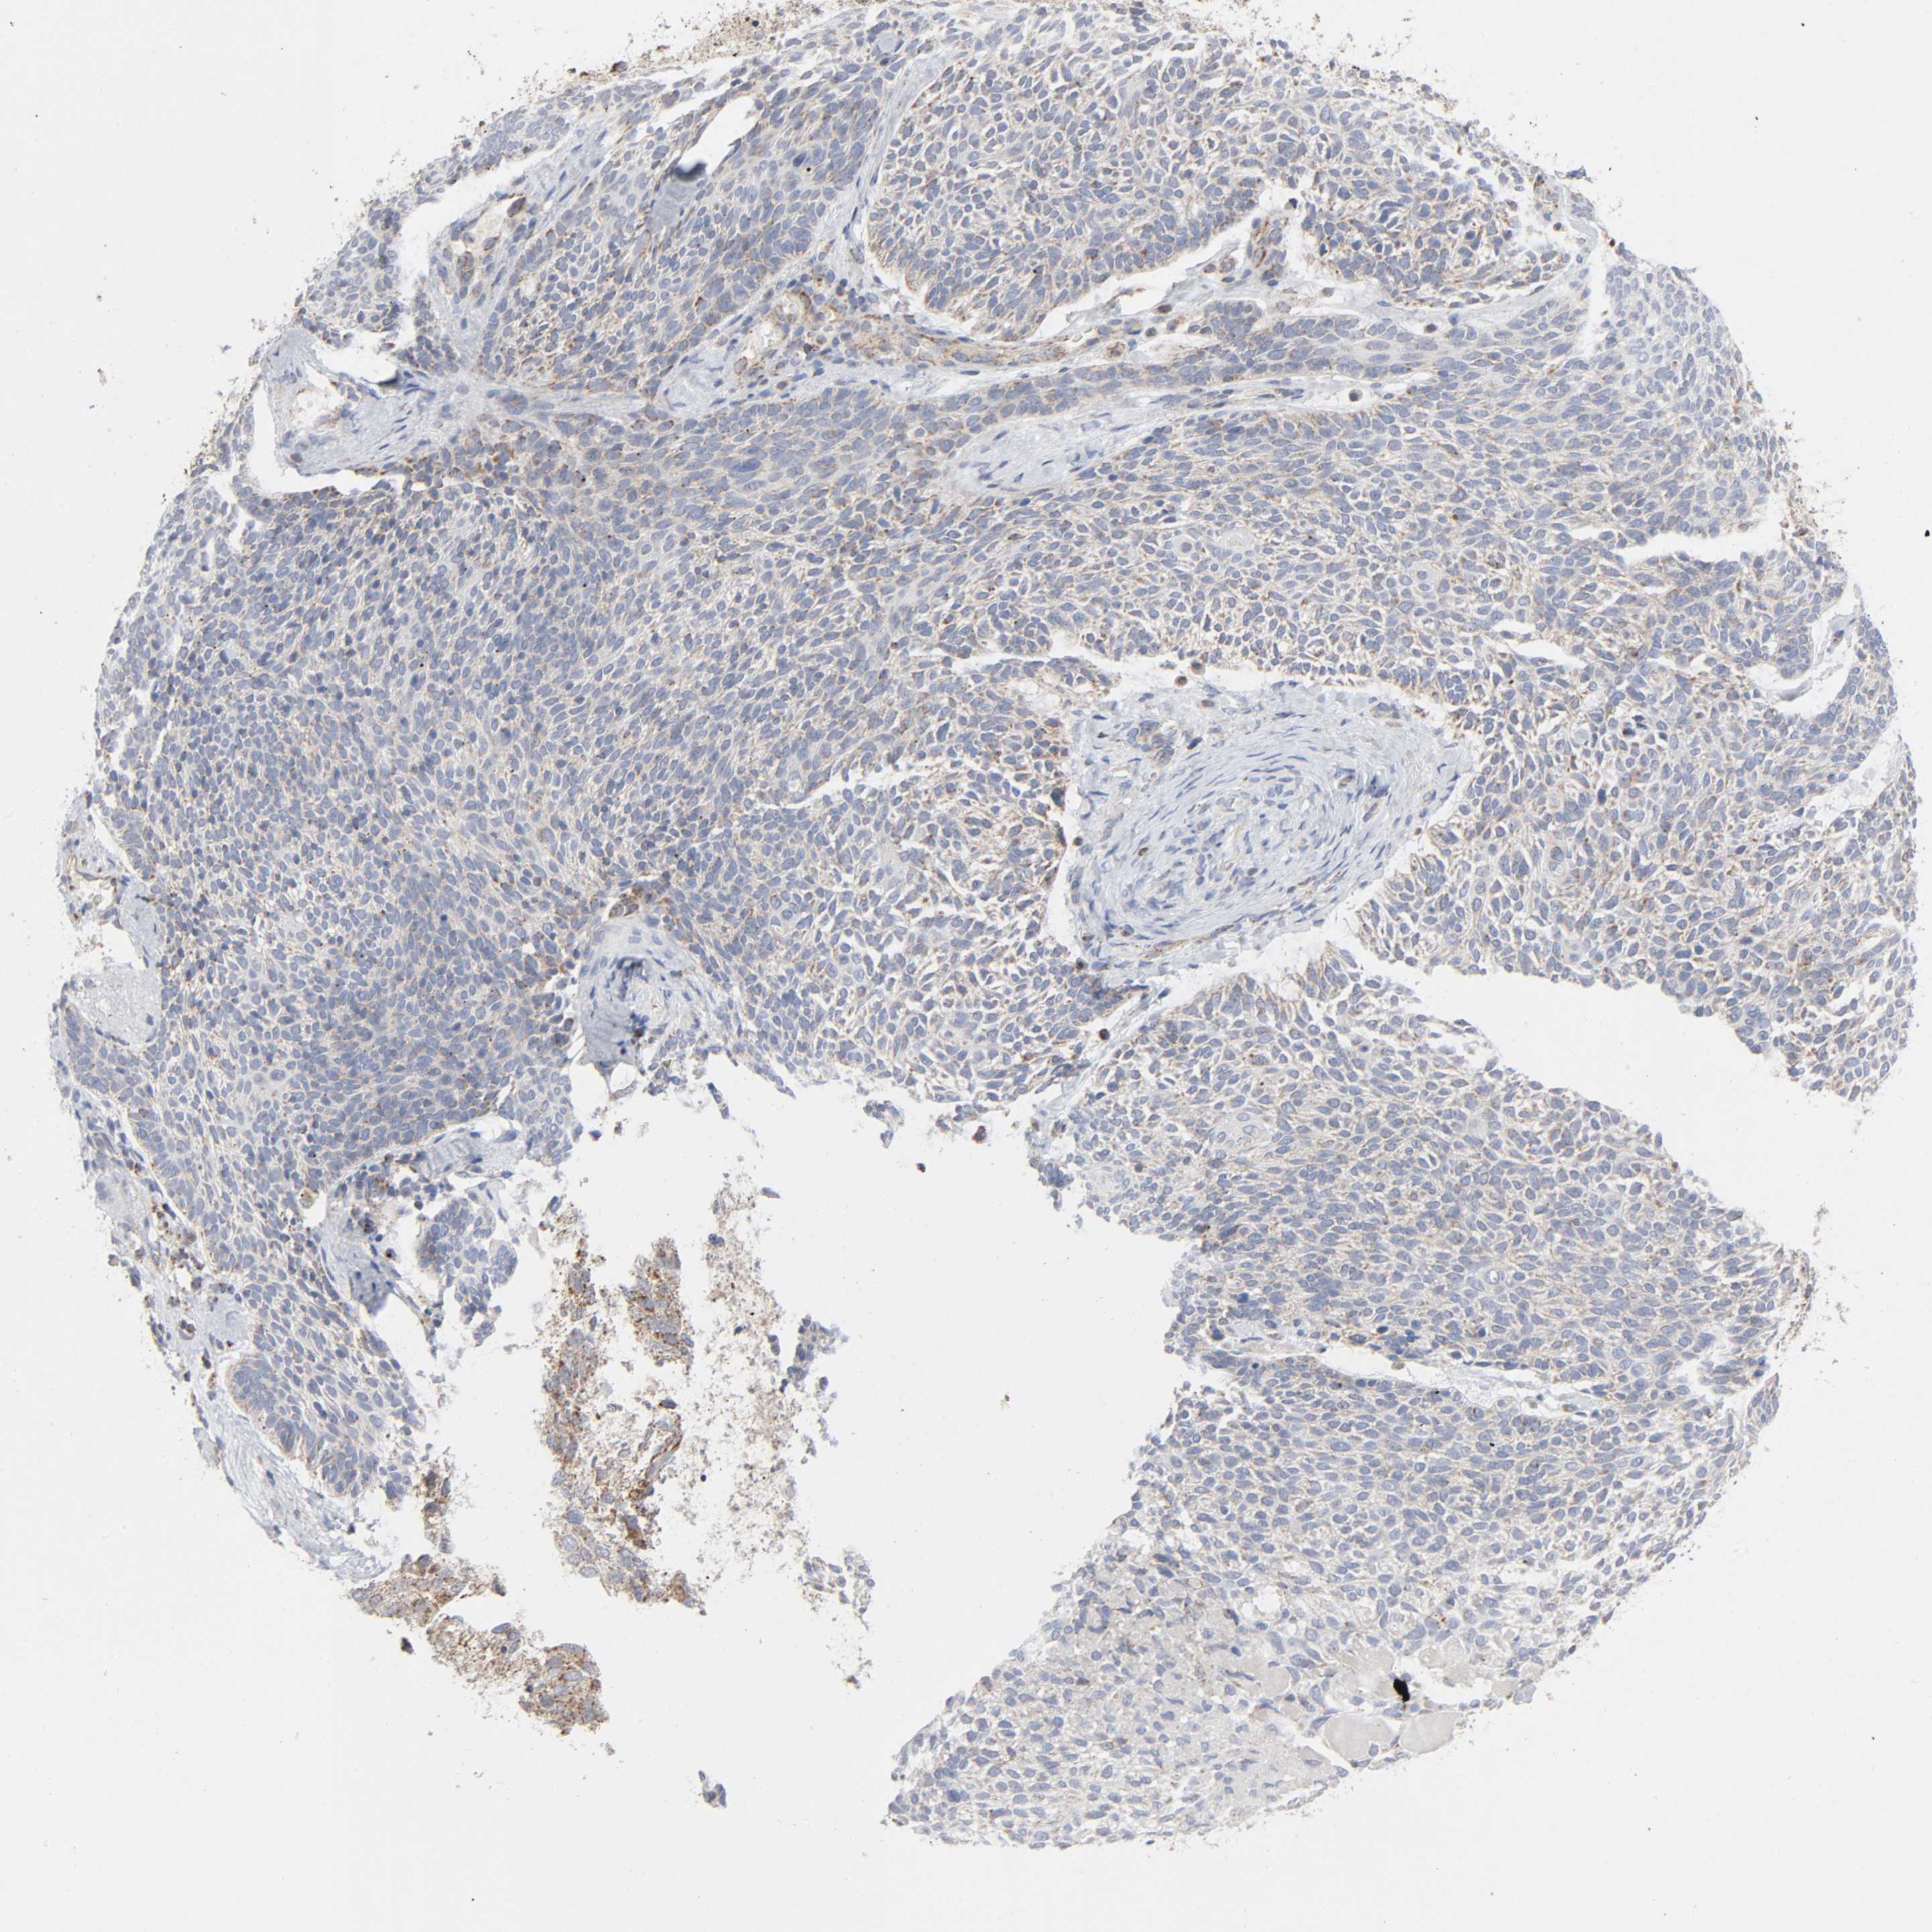

Basal cell and squamous cell cancer

SKIN CANCER - Protein expressioni

A mouse-over function shows sample information and annotation data. Click on an image to view it in a full screen mode. Samples can be filtered based on level of antibody staining by selecting one or several of the following categories: high, medium, low and not detected. The assay and annotation is described here.

Antibody stainingi

Antibody staining in the annotated cell types in the current human tissue is reported as not detected, low, medium, or high, based on conventional immunohistochemistry profiling in selected tissues. This score is based on the combination of the staining intensity and fraction of stained cells.

Each image is clickable and will lead to virtual microscopy that enables deeper exploration of all samples and also displays staining intensity scores, fraction scores and subcellular localization as well as patient and tissue information for each sample.

Antibody HPA004199

Antibody HPA076871

Squamous cell carcinoma, NOS

Basal cell carcinoma